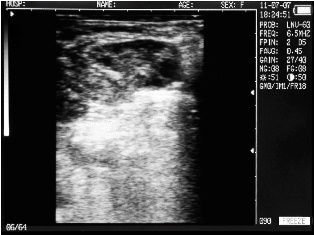

Ultrasound images of cows reproductive system, generated by a scanner Sonovet with rectal linear transducer.

Endometritis in the uterus of the cow